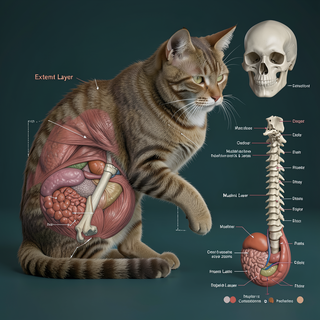

Creates ultra-detailed, multi-layer 3D anatomical visualizations from reference photos.Open

Creates ultra-detailed, multi-layer 3D anatomical visualizations from reference photos.Open

Transform photos into scientific anatomical illustrations.Open

Transform photos into scientific anatomical illustrations.Open